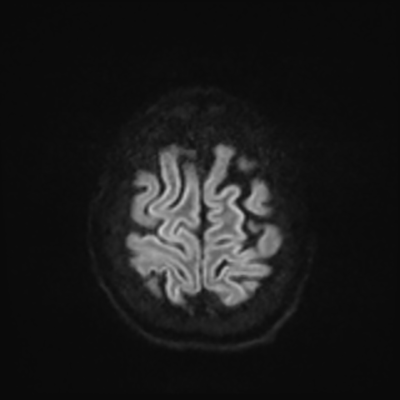

MRI brain (DWI)

You can clearly see diffuse cortical and basal ganglia diffusion restriction, and that of his deep cerebellar nuclei as well. The right occipital lobe abnormalities are a little more prominent, but then you remember that he is known to have had a right occipital stroke weeks ago.